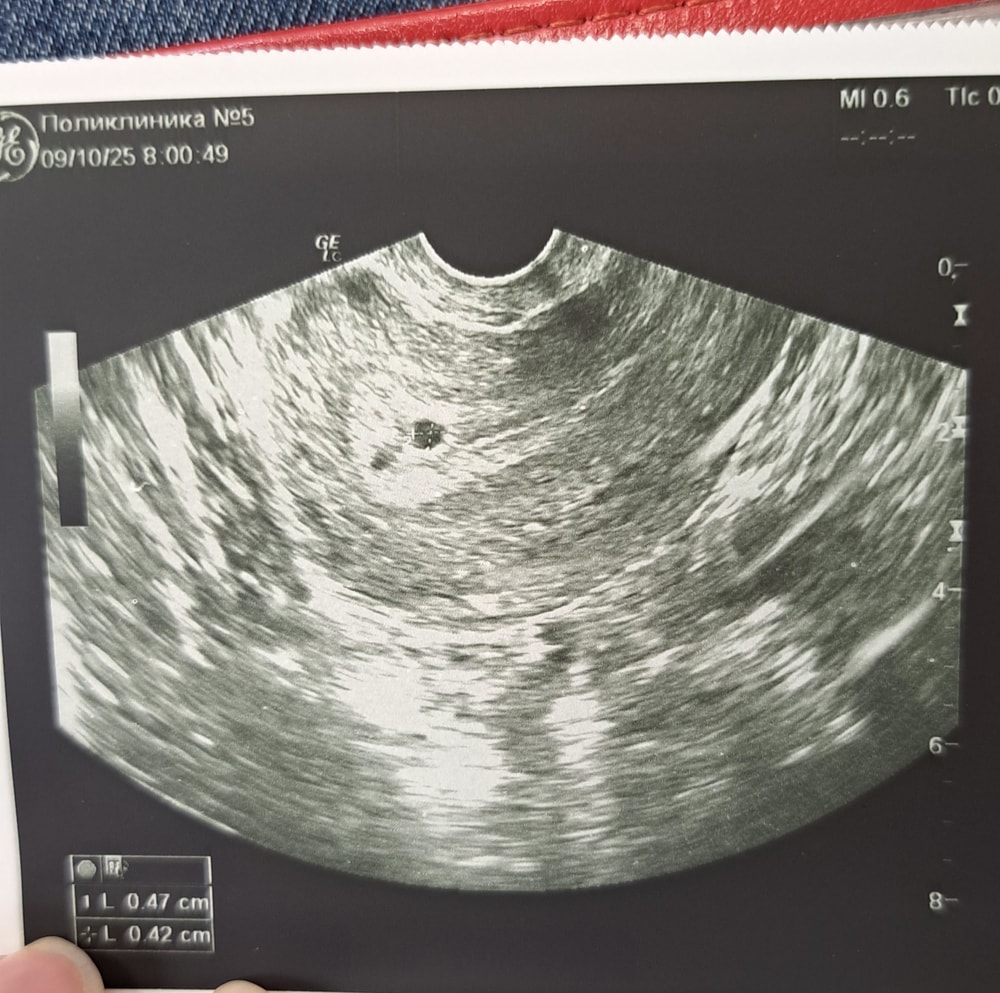

Описание забыла сфоткать. Но во всяком случае фоточка есть) ПЯ в матке)) ЖТ визуализируется,эмбрион пока не видно, такое узи мне делали в ведомственной поликлинике, а вот 17 я иду уже в женскую консультацию и там уже будет все ясно. При каком хгч видно эмбрион?